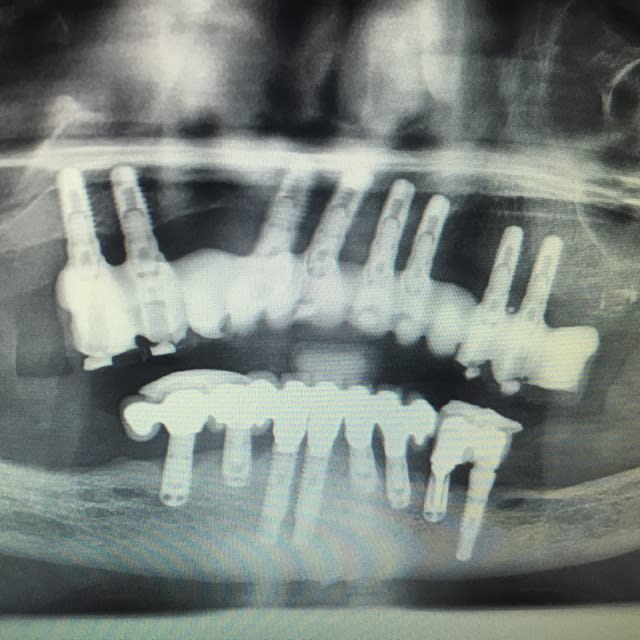

Quelle est cette marque d'implant ?

au maxillaire surtout !

et désolé pour la qualité des photos

camlog ?

oui, camelog...;-)